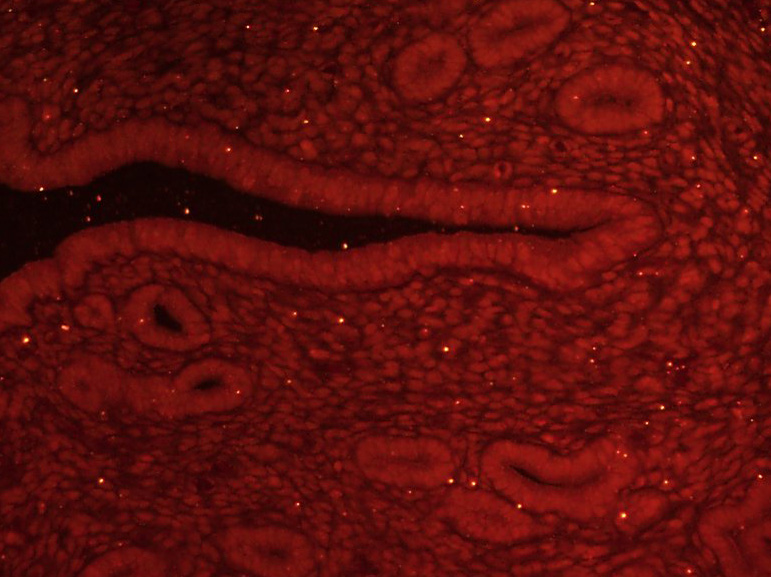

產(chǎn)品圖片

Paraformaldehyde-fixed, paraffin embedded (Mouse uterus); Antigen retrieval by boiling in sodium citrate buffer (pH6.0) for 15min; Block endogenous peroxidase by 3% hydrogen peroxide for 20 minutes; Blocking buffer (normal goat serum) at 37°C for 30min; Incubation: Anti-GLI1 Antibody, conjugated (bs-1206R-BF555) at 1:100 overnight at 4°C; DAPI (5ug/ml, blue, C-0033) was used to stain the cell nuclei.